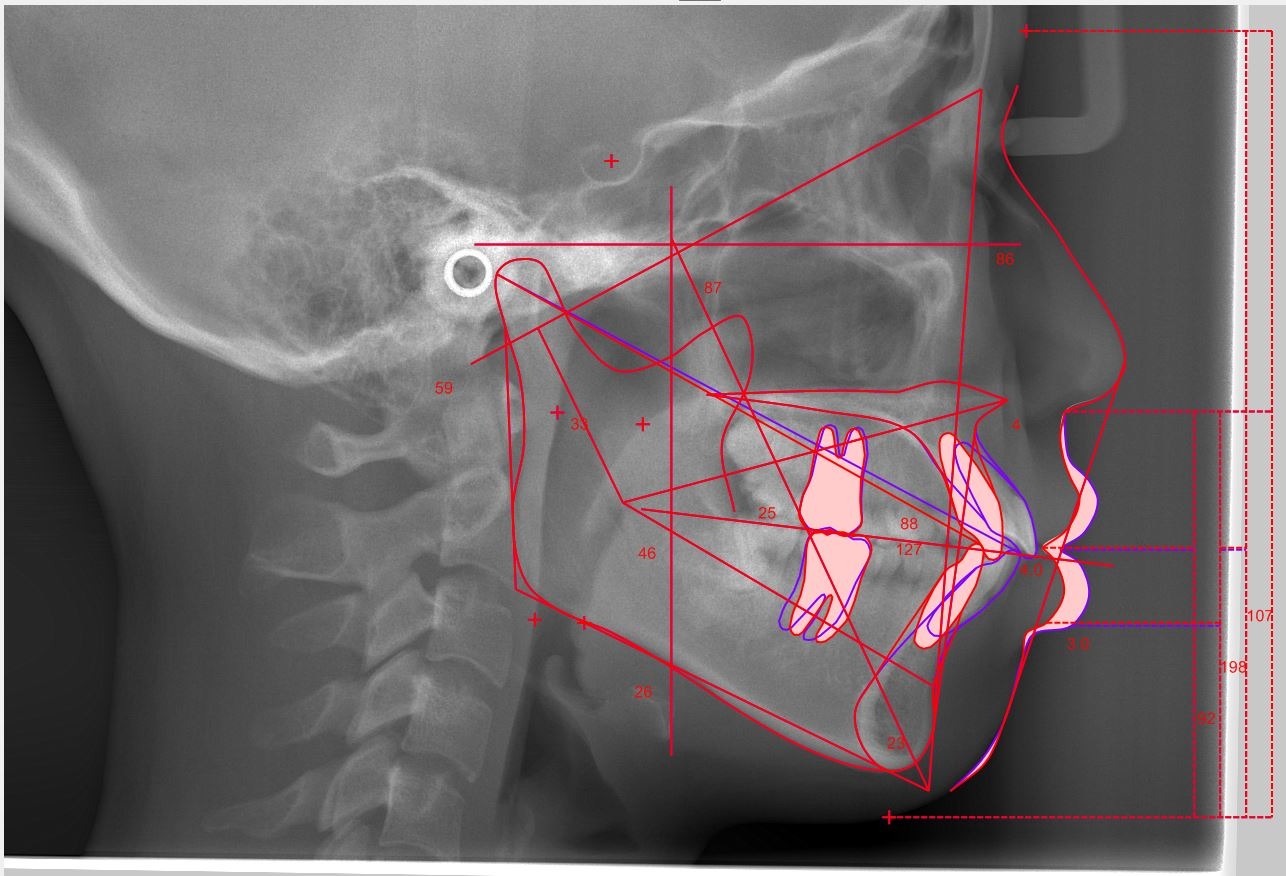

頭部X線規格写真(セファロ)

骨格・歯の位置を数値化して分析

安全ライン(下げ幅の上限)算出

歯根や骨を守る安全な移動量を計算

当院が出っ歯矯正で大切にしているのは、前歯をどこまで下げるかの見極めです。

出っ歯の見え方は、前歯の傾きだけでなく、あごの前後位置(骨格)も関係しています。

そのため当院では、歯と骨格の両面から”ベストな下げ幅”を見極める診断を行っています。